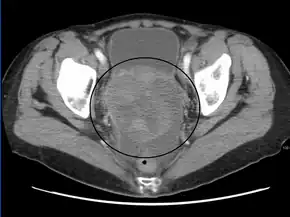

A CT scan shows a solid mass in the pelvis in stage I without yet established blood vessels and septa[23]

The preliminary diagnosis begins with a pelvic examination, serum tumor marker test and imaging. Physicians may feel a large palpable mass or lump in lower abdomen upon insertion of the gloved fingers into the vagina. To further identify the histologic subtypes of OGMTs, blood samples of patients are collected to analyse the serum level of biomarkers released by the tumor cells. A surge in the plasma levels of human chorionic gonadotropin and alpha-fetoprotein is indicative of OGMTs.[1] Lactate dehydrogenase, alkaline phosphatase and cancer antigen 125 might potentially increase as well.[24] To visualize the location and morphology of the tumor, transvaginal ultrasonography is usually employed.[1] The most characteristic appearance is a parenchymal-like heteroechoic mass with sharp borders and high vascularization.[1] Computed tomography would produce stacked image inside the peritoneal region of the body to visualise the lobular pattern of the tumour.[1] Usually for dysgerminoma, solid mass being compartmentalized into lobules with enhancing septa may be evident for haemorrhage or necrosis.[1]